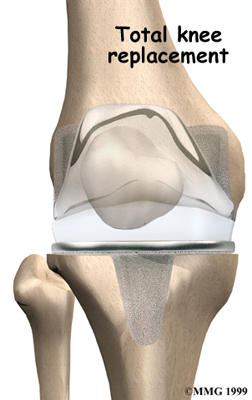

Artificial Knee Replacement

An artificial knee replacement is the ultimate solution for advanced knee OA.

Surgeons prefer not to put a new knee joint in patients younger than 60. This is because younger patients are generally more active and might put too much stress on the joint, causing it to loosen or even crack. A revision surgery to replace a damaged prosthesis is harder to do, has more possible complications, and is usually less successful than a first-time joint replacement surgery.

Related Document: FYZICAL Bryan's Guide to Artificial Joint Replacement of the Knee